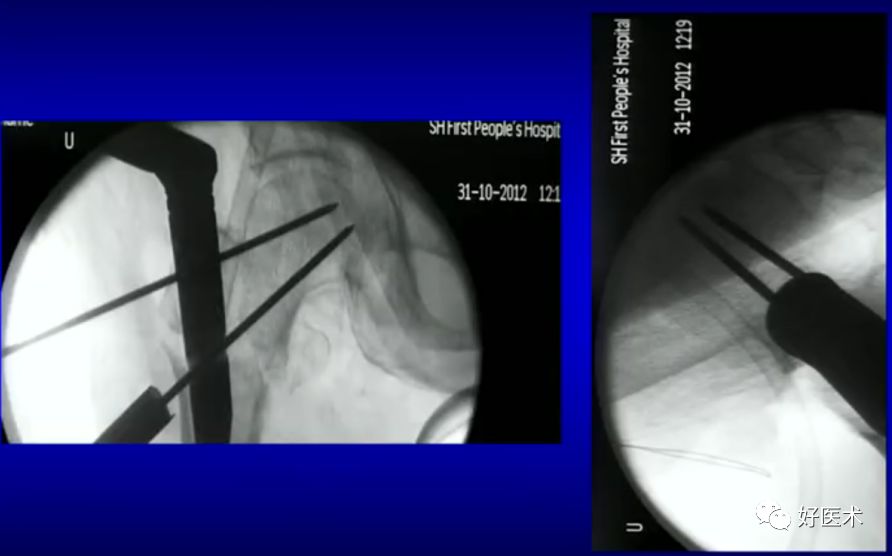

6.正确的股骨颈正侧位

侧卧位如何透股骨颈的侧位:

-

标准侧位

球管20-30°

侧卧位行转子间骨折固定

病例:男,34岁,高处坠落伤,仅骨折余正常

处理方法:

术前牵引

开口、定位

术中过程